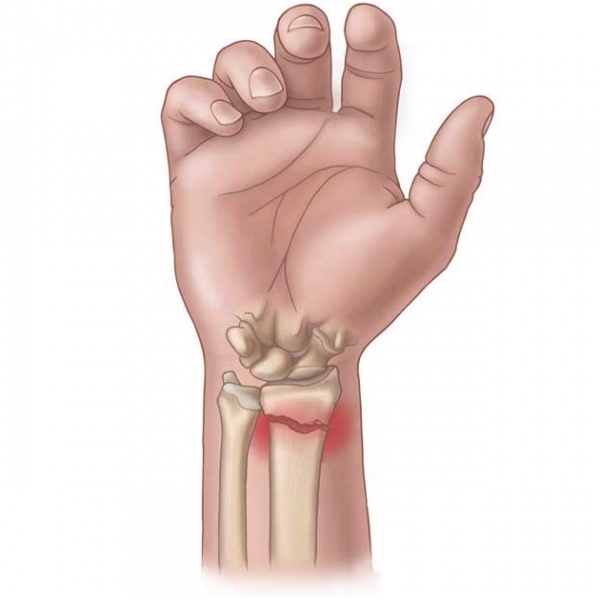

Luxação.

A luxação é uma lesão caracterizada pelo deslocamento parcial ou completo de um ou mais ossos em uma articulação. Normalmente, tem origem traumática, em decorrência

A luxação é uma lesão caracterizada pelo deslocamento parcial ou completo de um ou mais ossos em uma articulação. Normalmente, tem origem traumática, em decorrência